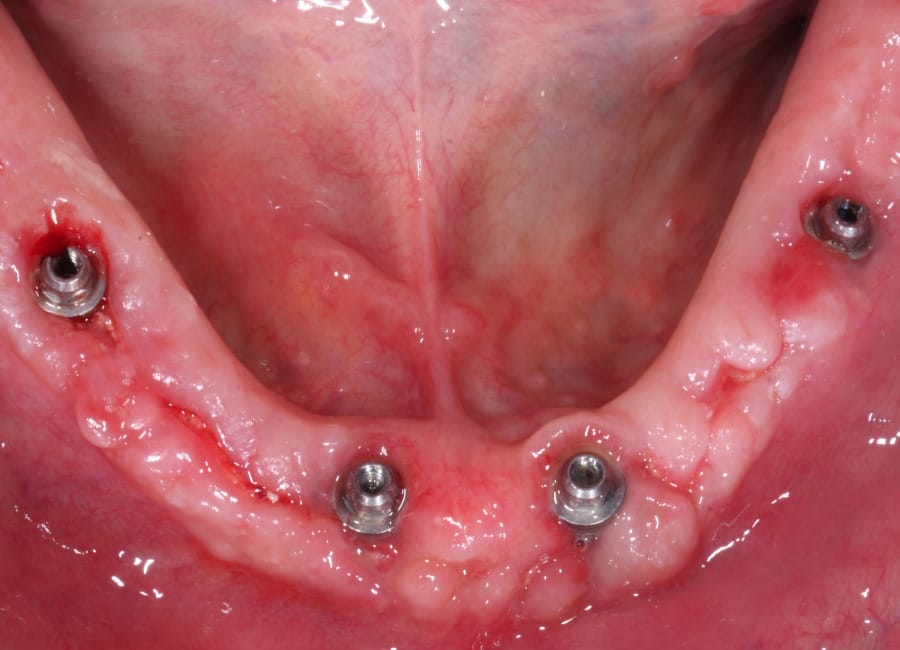

Surgical phase